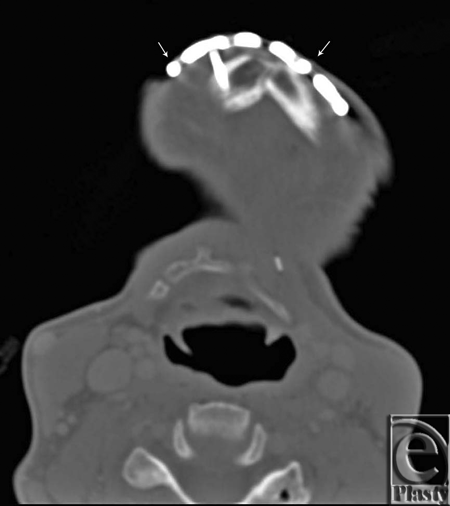

Twelve months postoperatively, she developed thinning of the chin skin and exposure of the anterior portion of the mandibular plate. CT scan confirmed bony union of the free fibula to the mandible bilaterally. Her skin was very thin throughout the neck and, interestingly, the skin had epithelialized under the exposed reconstruction plate. At this time it was decided to approach her plate directly and in a manner that would safely not disrupt the bone graft and epithelialized skin below the reconstruction plate. A small extension of the skin opening was performed in the lateral direction on both sides. The exposed screws were removed transcutaneously. The titanium reconstruction plate was then removed with a single cut on both sides, immediately proximal to the point of initial exposure using a Large Surgical Pin Cutter. The plate was then removed and the skin was closed in simple fashion with 5-0 nylon sutures that were removed 2 weeks later. The wound went on to heal well.

| Figure 3. Preoperative computed tomographic scan. Arrows indicated where cuts were made with large surgical pin cutters to remove the exposed portion of the reconstruction plate. |